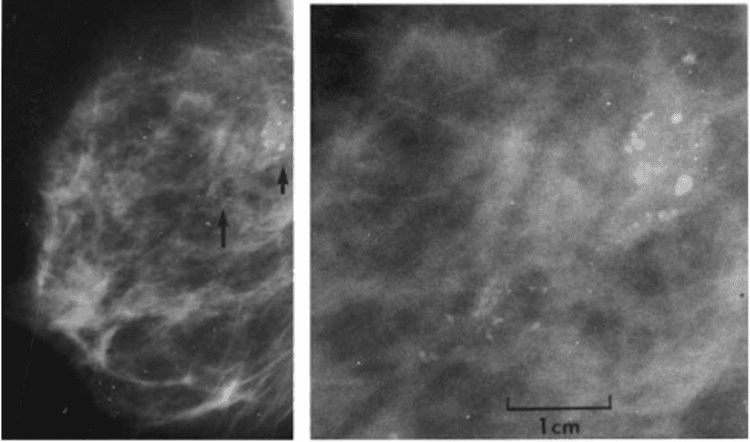

Vôi hóa hay vi vôi hóa là gì?

Vi vôi hóa hay vôi hóa là sự lắng đọng các khoáng chất có thể có trong cả các tổn thương tuyến vú không phải ung thư và các tổn thương ung thư. Chúng có thể thấy trên cả phim chụp nhũ ảnh hoặc dưới kính hiển vi. Vì một số vôi hóa được thấy trong các vùng chứa ung thư, nên sự hiện diện của chúng trên phim chụp nhũ ảnh là dấu hiệu chỉ điểm để sinh thiết vào vùng này.

Sau đó, bác sĩ giải phẫu bệnh quan sát mẫu mô được lấy ra và chắc chắn rằng mẫu đó có chứa vôi hóa. Nếu có vôi hóa, bác sĩ hiểu rằng mẫu sinh thiết đã lấy đúng vào vùng tổn thương (chính là các vùng bất thường có chứa vôi hóa trên nhũ ảnh).

Vi vôi hóa và vôi hóa chỉ quan trọng vì đôi khi chúng được thấy trong các vùng có chứa ung thư. Khi chúng được tìm thấy đơn độc (không có các biến đổi đáng lo ngại trong các ống hoặc tiểu thùy), thì chúng không quan trọng.